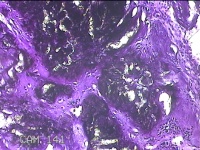

左肘关节肿物

左肘关节肿物(痛风石)

发现左肘关节肿物2年余。

灰白暗红色组织5.5x4x2.3cm一块,表面带梭形皮肤5.5x3.3cm,皮下见肿物5.5x2x1.3cm一个,切开肿物,内见大量石灰样物,内壁粗糙。